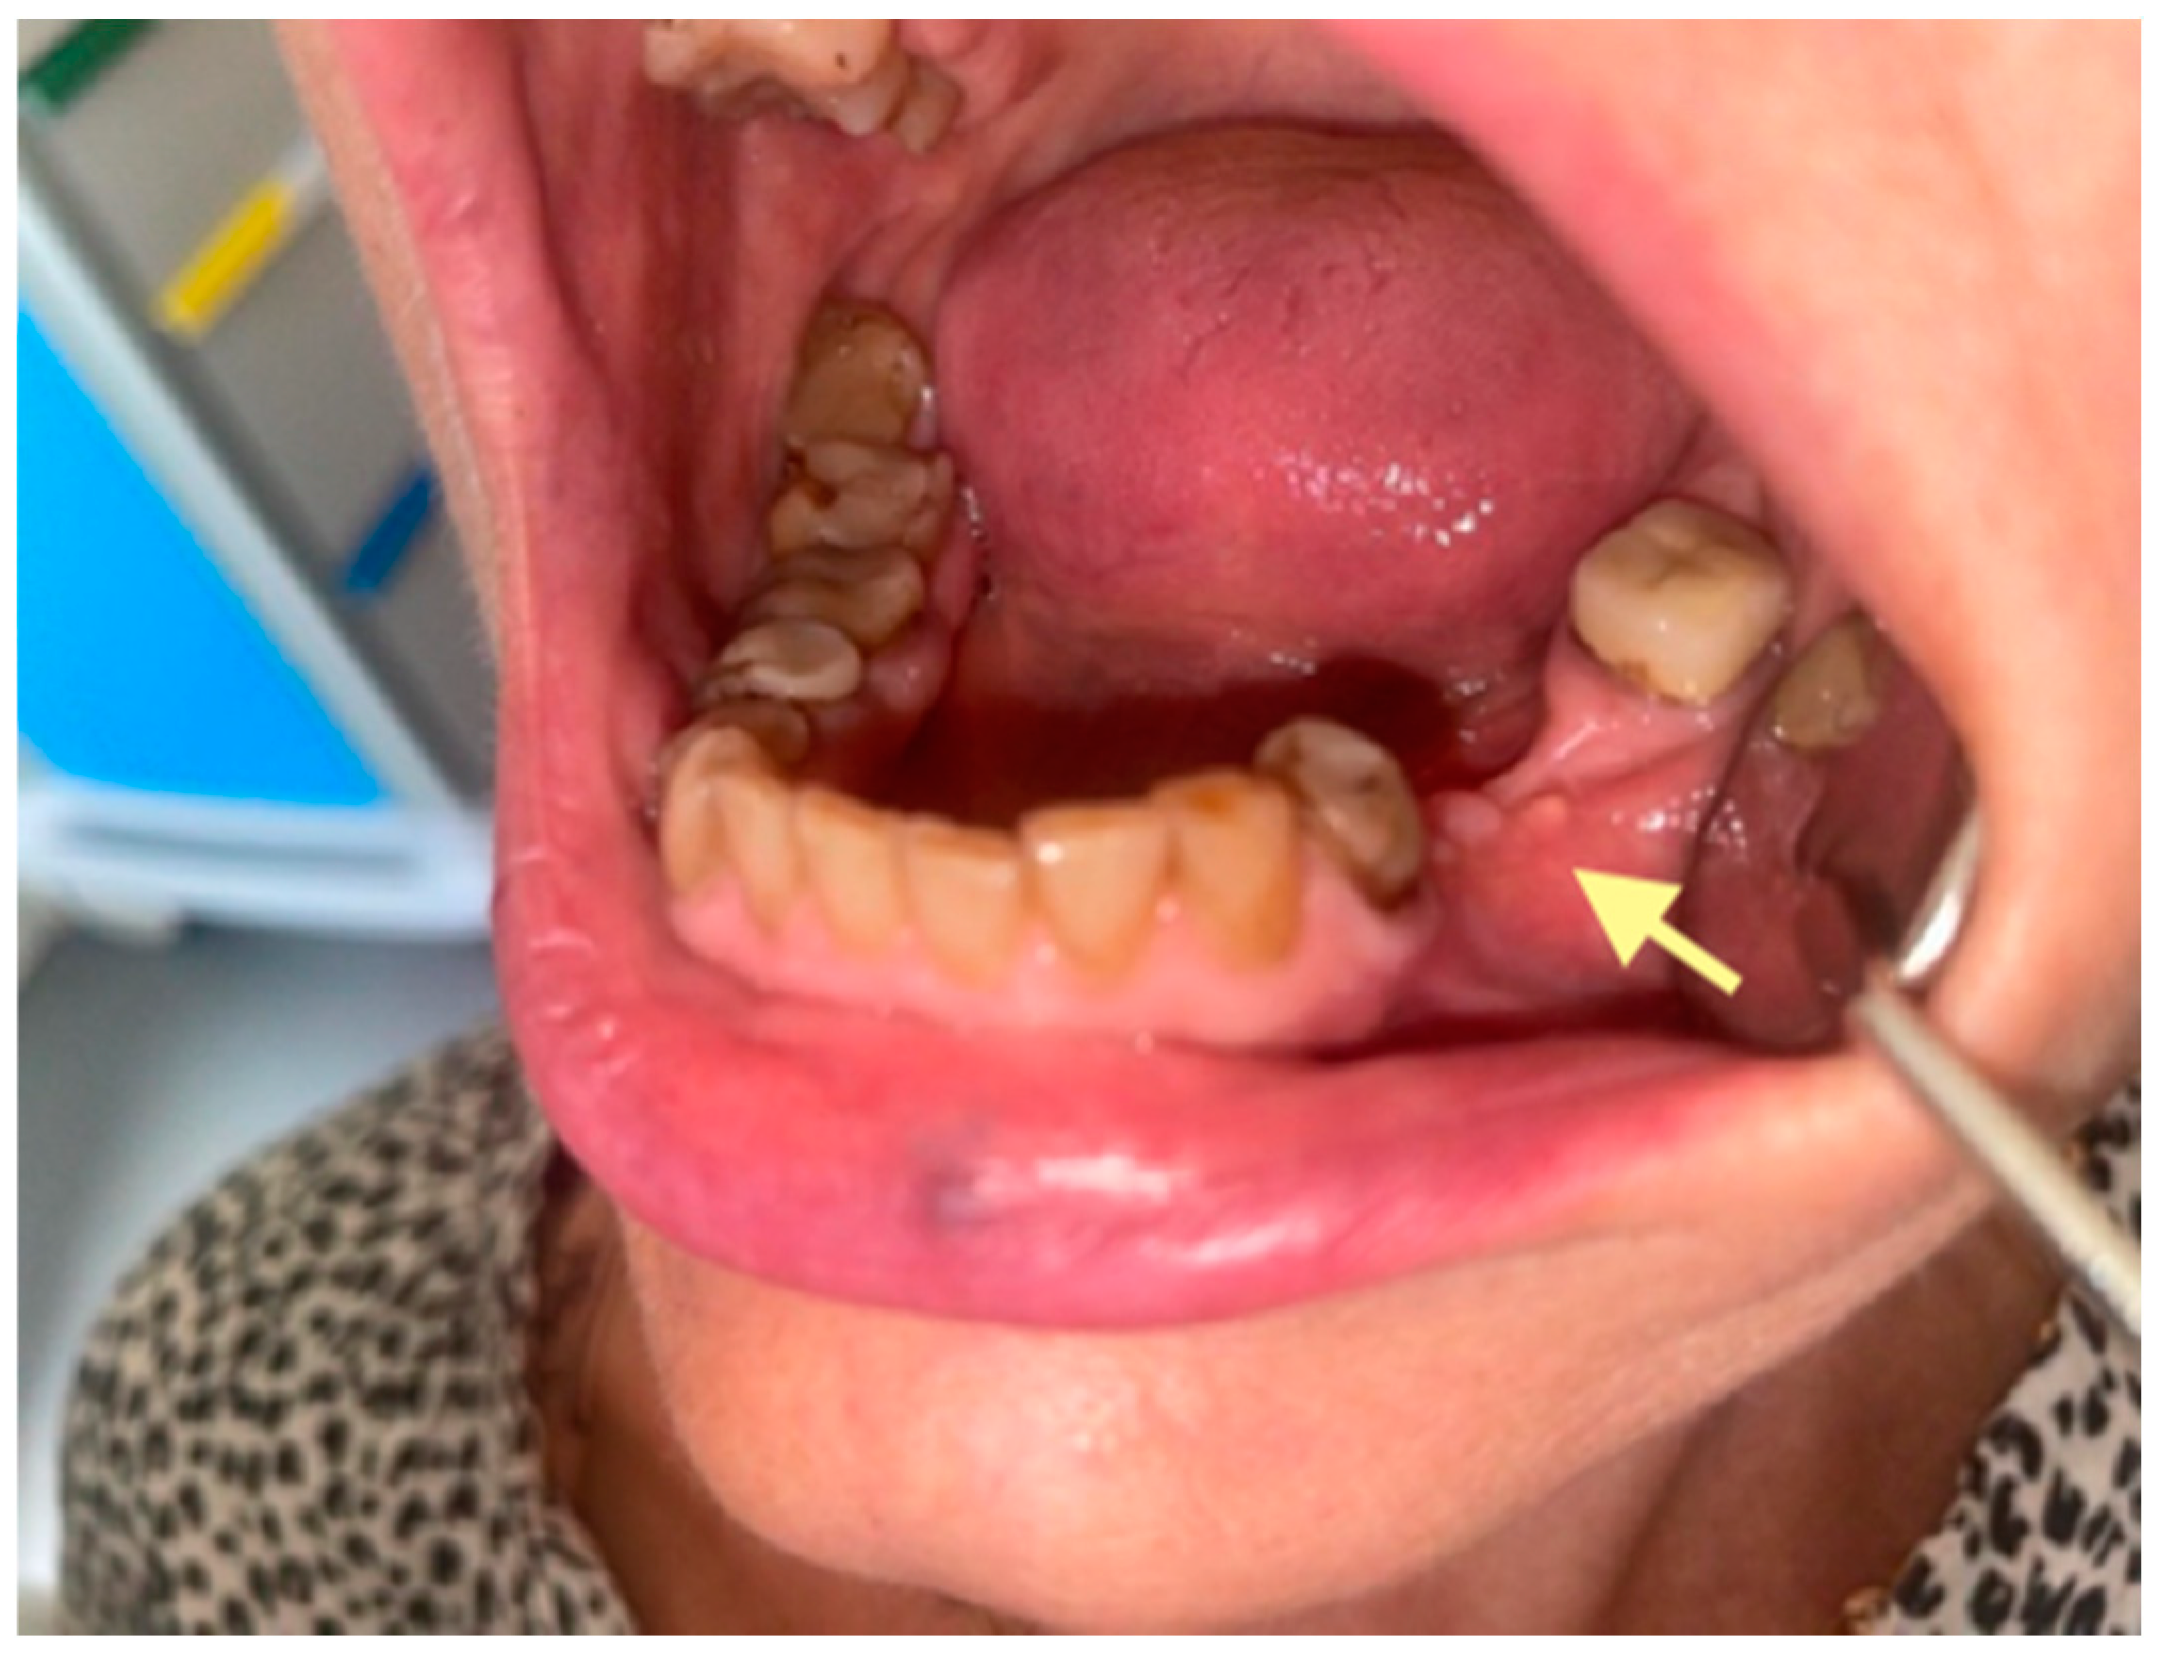

The second patient was an 82-year-old female with osteonecrosis of the mandible in the fourth quadrant, which developed after the removal of tooth 46 on November 2023 (see Figure 4). The patient had second-stage osteonecrosis of the jaw. Initially, the patient underwent a revision of the socket of the extracted tooth and was prescribed antibacterial therapy. Despite this treatment, the patient continued to complain of a non-healing wound on the lower jaw in the area of the molars with periodic purulent discharge. In addition, these complaints were supplemented by a complaint of an intraoral fistula on the lower jaw in the area of the frontal teeth. Therefore, in May 2024, the patient underwent surgery (sequestrectomy and application of A-PRF). After the operation, the patient’s condition improved, purulent discharge from the wound stopped, the pain ceased, and the postoperative wound closed completely (see Figure 4). However, after a month, dehiscence of the wound was noted. Therefore, it was decided to repeat the operation, performed on 4 April 2025, and, in addition, to expand the scope of the surgical procedure, the sequestrectomy of the lower jaw was performed not only in the region of dd45-46 but also in the central area, simultaneously applying A-PRF. As a result of the treatment, the surgical wound on the lower jaw in the area of the molars on the right healed completely, but in the area of the incisors, it closed partially (see Figure 5 and Figure 6).

Control visit of the patient after the second surgery, one month after the second operation performed on 28 May 2025.